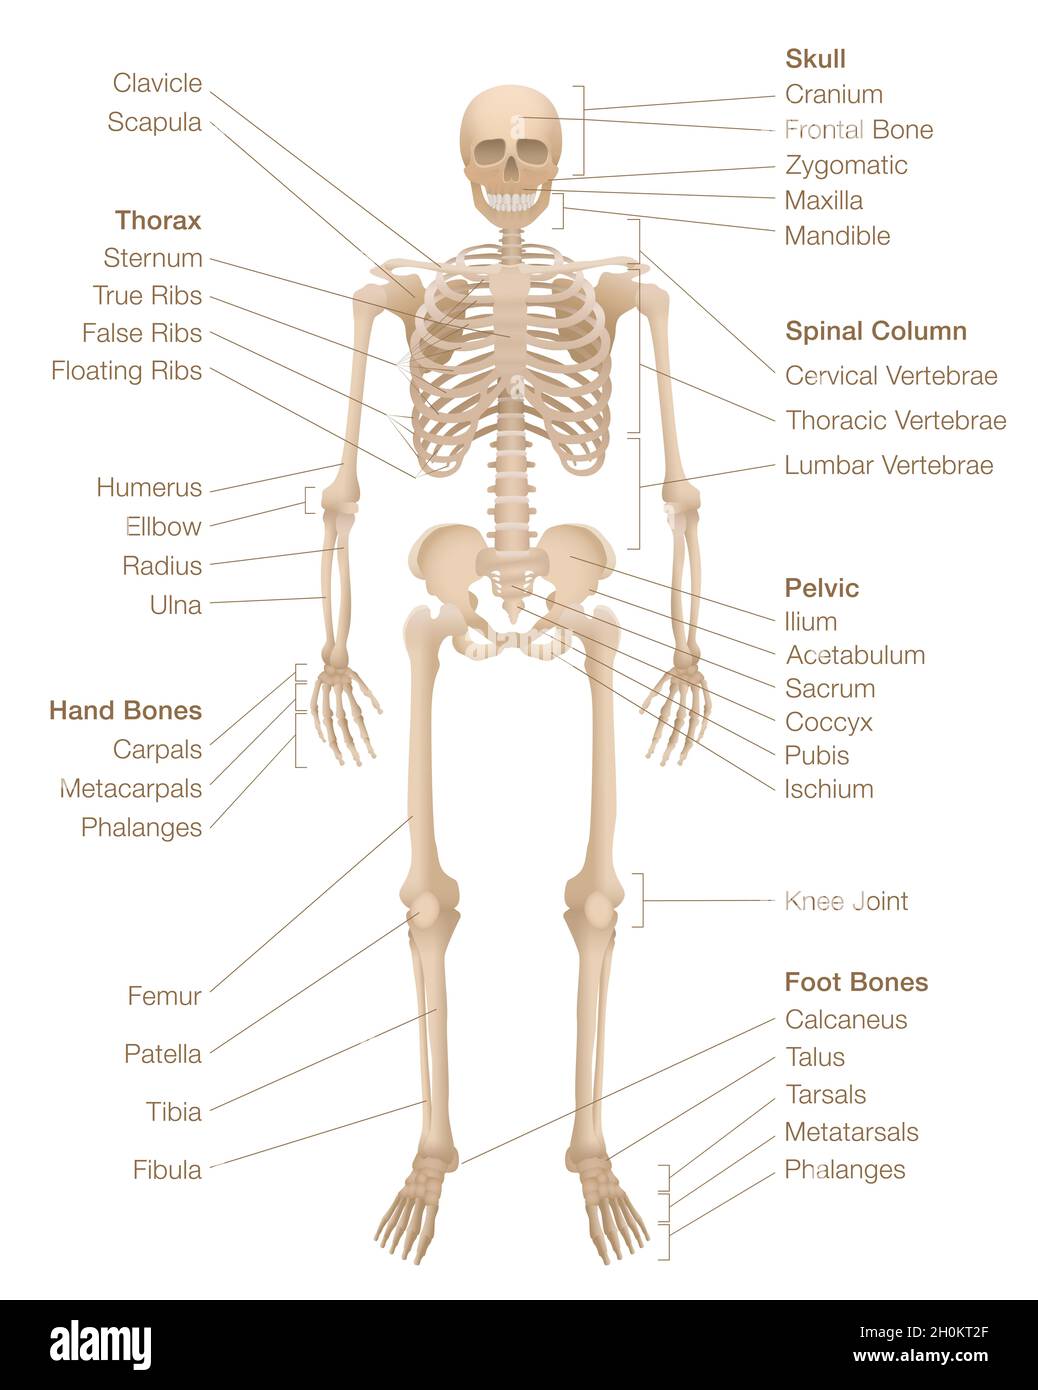

RF2GNRHN3–Anatomie du squelette - carte du système squelettique humain - marquée avec les os les plus importants comme le crâne, la colonne vertébrale, le bassin, le thorax, les côtes, sternum, main.

RF2H0KT2F–Diagramme squelette humain.Système squelettique marqué avec os nommés, crâne, colonne vertébrale, bassin, thorax,côtes, sternum, os des mains et des pieds, clavicule.